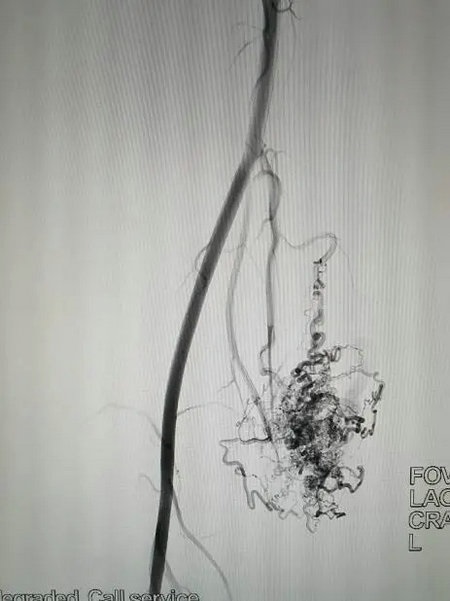

动静脉畸形的辅助检查包括超声、CT、磁共振、动脉造影等技术。目前来说,增强CT(图5)及DSA(图6)可明确病变累及的部位大小、范围,是确定诊断及治疗的重要方法。特别是对外观不易发现检查出的骨及盆腔动脉静脉畸形(图7),能避免误诊及漏诊。

▲ DSA右腿AVM(图6)